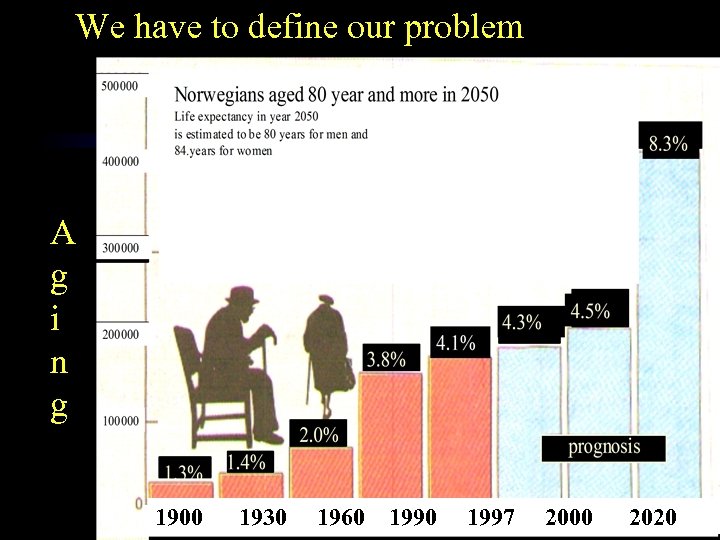

We have to define our problem A g i n g 1900 1930 1960 1997 2 2000 2020

We have to define our problem A g i n g 1900 1930 1960 1997 2 2000 2020

Cooper C, Campion G, Melton LJ (1992) Osteoporosis Int; 2: 285 -289 • 6. 25 million is an estimated number of hip fractures world wide by 2050 • Increasing world population and increasing life expectancy seems to be the most important reason for this increase

Cooper C, Campion G, Melton LJ (1992) Osteoporosis Int; 2: 285 -289 • 6. 25 million is an estimated number of hip fractures world wide by 2050 • Increasing world population and increasing life expectancy seems to be the most important reason for this increase